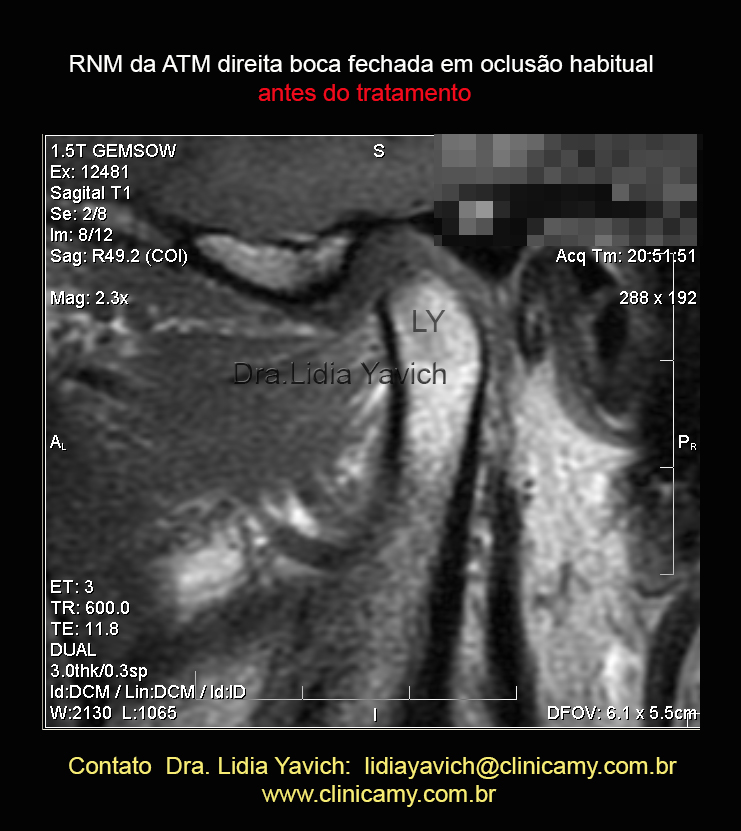

Este corte sagital interno da RNM da ATM direita em boca fechada mostra compressão e retroposição do côndilo mandibular. Observa-se uma faceta superior na cabeça mandibular.

LEMBREMOS QUE estamos olhando uma imagem bidimensional e que temos que entender que a COMPRESSÃO É TRIDIMENSIONAL.

Este outro corte sagital da RNM da ATM direita em boca fechada evidencia ainda mais a compressão e retroposição do côndilo mandibular. Observa-se uma faceta superior na cabeça mandibular.